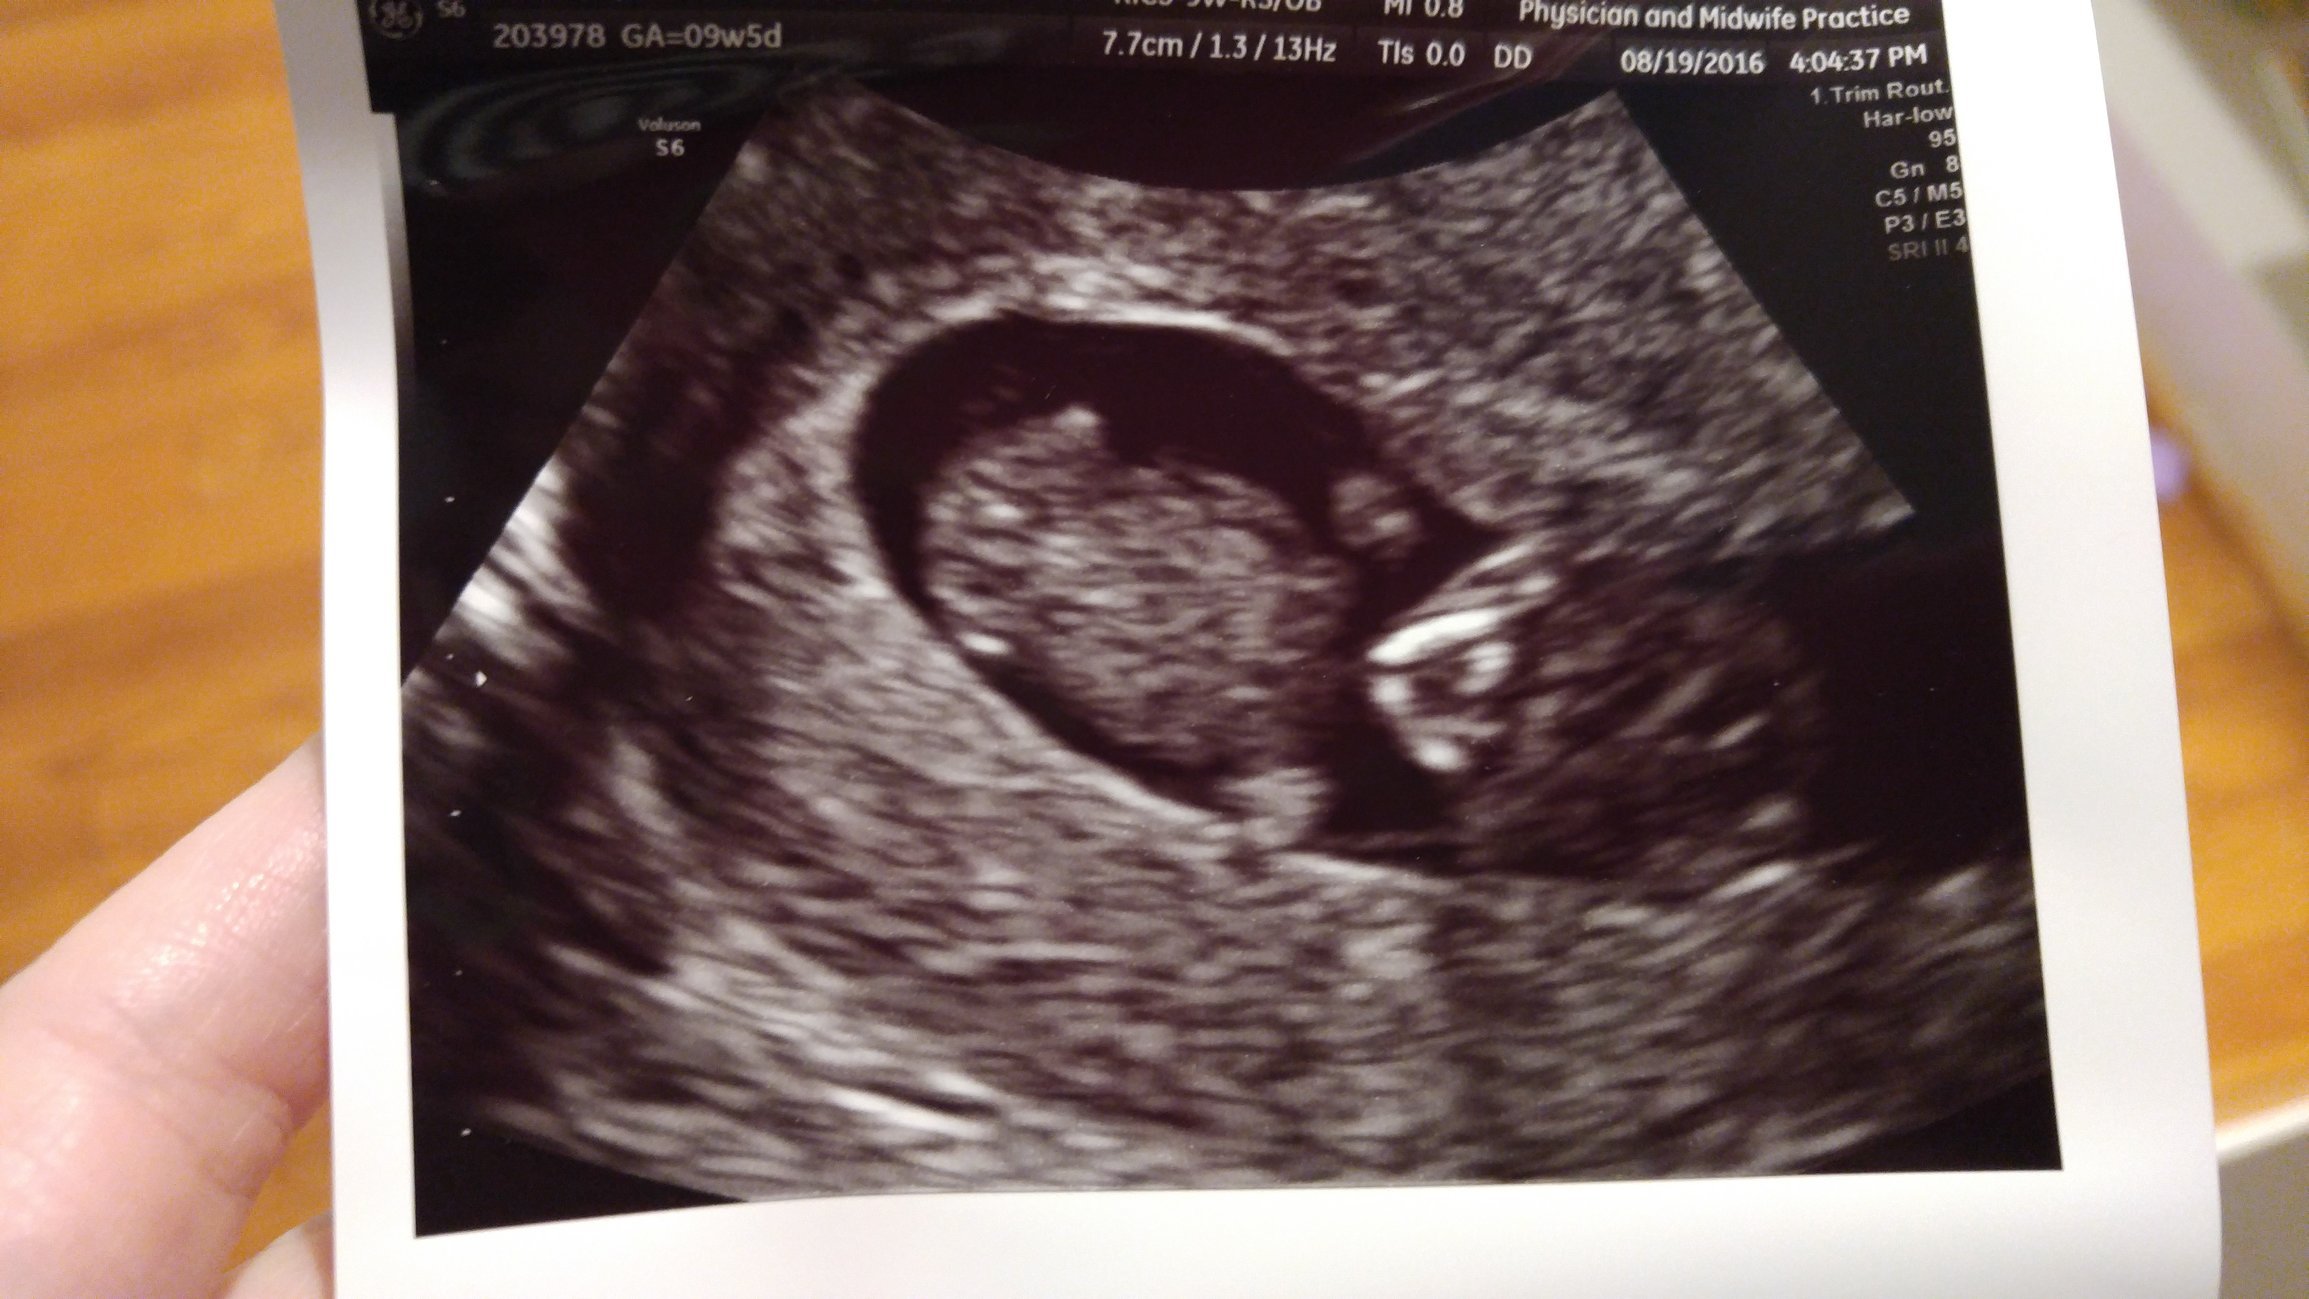

Finally decided to join the AW club today. We have had several ultrasounds but today was the first time that the babies looked like little babies. They were squirming all over the place and not staying still for the poor ultrasound tech at all. Both are measuring on track and had great heartbeats!

*Edited to add - I am 11 weeks and 4 days today. Also - sorry for the giant picture, I'm not sure how to make it smaller...